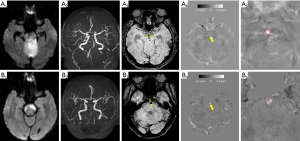

All images were saved in the nifti format (https://nifti.nimh.nih.gov/nifti-1/) for quantitative susceptibility calculation and analysis of the region of interest (ROI). The QSM [with the unit of parts per million (ppm)] was performed using the STI Suite toolbox (v2.2) in MATLAB (Mathworks, Natick, MA, USA) (6), and then loaded in 3D Slicer (8) (https://www.slicer.org/) for ROI analysis. For each participant, the thrombus ROI was manually drawn on the hyperintense region on 1 central axial slice in the BA of the QSM image. As the QSM provides relative rather than absolute values of magnetic susceptibility, the susceptibility of thrombi was normalized using the white matter reference (9). The reference ROI was drawn on one axial slice in the normal-appearing white matter in bilateral centrum semioval (Figure S1). The thrombus susceptibility value for each participant was recorded as the difference between the mean susceptibility values of the thrombus ROI and the reference ROI. The ROI drawing and QSM quantification output were performed by 2 investigators (J.C. and Z.Z.) who were blinded to the clinical data (10).

The SWI was generated from gradient-echo data using the vendor-provided SWIp sequence. The SVS was defined as in previous research on SWI by hypointense signs in the corresponding symptomatic occlusive vessels (2). The diameter of the SVS-related hypointense signal was measured on SWI, using the maximum radial distance of the hypointense vessel (4). The SWI analysis was performed on an image viewer (RadiAnt DICOM viewer, https://www.radiantviewer.com/).

The susceptibility of the hyperintense signal at BA (corresponding to the SWI hypointense signal) on QSM is also described in Figure 2. The interobserver agreement of the mean thrombus susceptibility measured by the intraclass correlation coefficient was 0.966. The BA thrombus’s susceptibility in participants with cardioembolic stroke was significantly higher than that in those with non-cardioembolic stroke (0.42±0.09 vs. 0.22±0.11 ppm, P<0.001). The ROC curve analysis showed that the area under the curve (AUC) of thrombus susceptibility was 0.89 (95% CI: 0.80 to 0.99, P<0.0001). The optimal cutoff value for the susceptibility of BA thrombus on QSM while identifying a cardioembolic stroke was 0.33 ppm (Figure 3). Furthermore, the QSM susceptibility (≥0.33 ppm) yielded a sensitivity, specificity, positive predictive value, and negative predictive value for the cardioembolic stroke of 81.8% (95% CI: 48.2% to 97.7%), 81.3% (95% CI: 63.6% to 92.8%), 60.0% (95% CI: 40.9% to 76.5%), and 92.9% (95% CI: 78.6% to 97.9%), respectively.